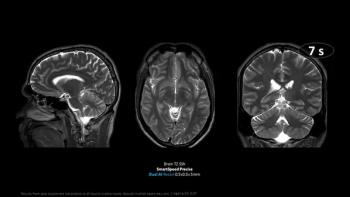

The deep learning reconstruction software reportedly facilitates accelerated MRI scanning and significantly enhanced image sharpness.